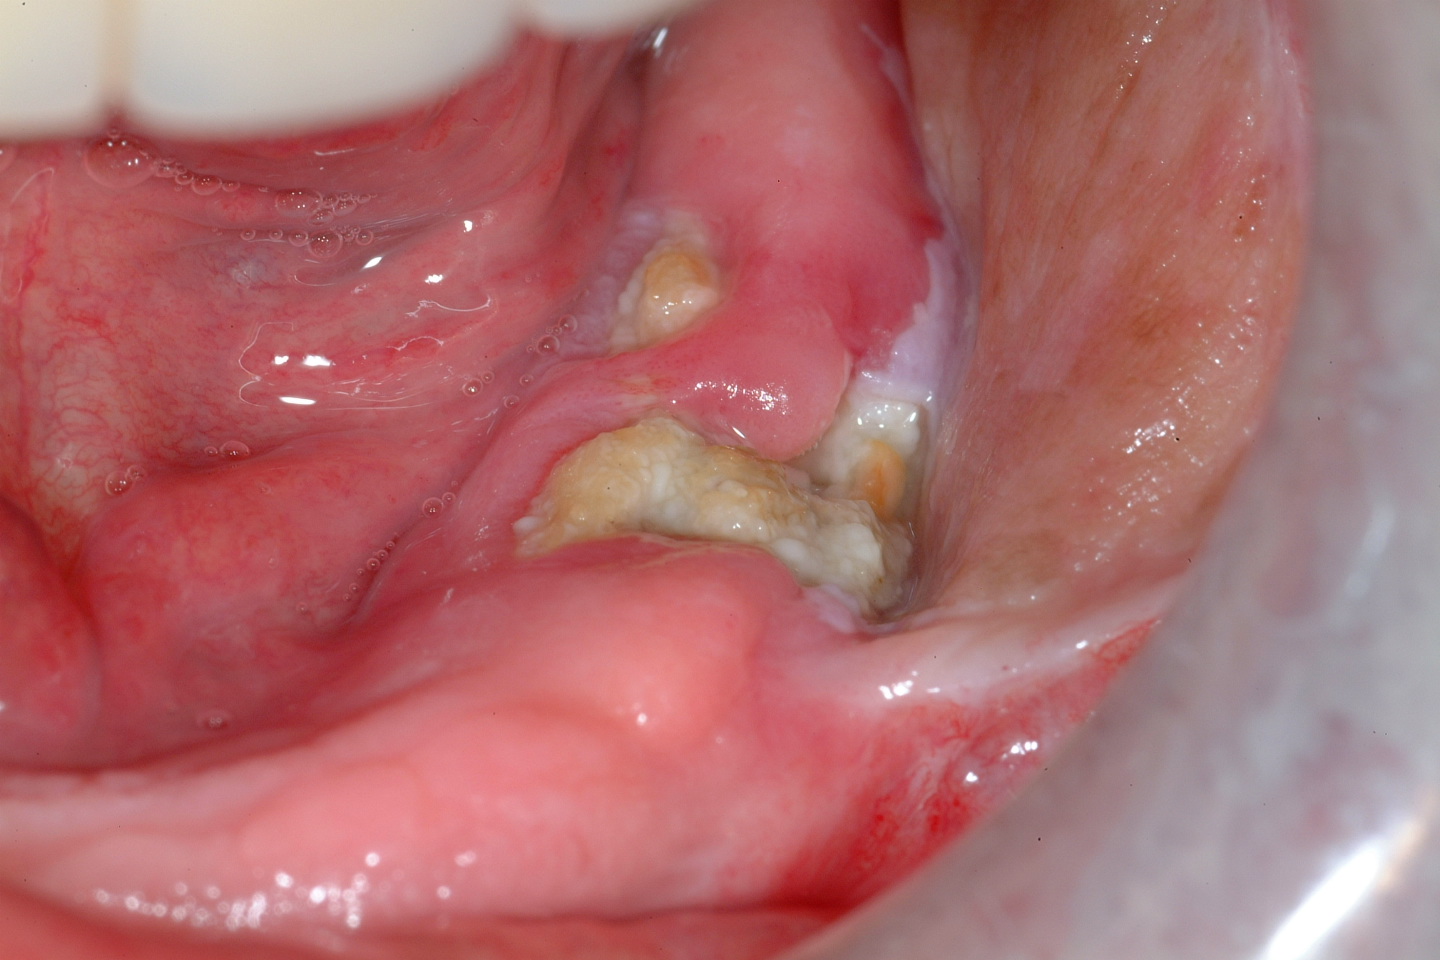

Figure 1, Figure 2 and Figure 3 show examples of different ORN conditions.

The signs and symptoms of osteonecrosis of the jaws (ONJ) include exposure of necrotic bone, ulceration and mucosal (soft tissue in the mouth) necrosis without healing tendencies, accompanied by pain. Depending on the underlying cause, acute symptoms may include swelling, infection or abscess, mucositis, trismus, disturbed sensation. Over time an oro-cutaneous fistula may develop from chronic infection, a pathological fracture of the mandible may occur, teeth may be lost and pieces of necrotic bone (such a piece is called a sequestrum) may be shed, usually through the mucosa.

ORN can be defined as irradiated bone which becomes devitalised and exposed through the overlying skin or mucosa without healing for three months, without recurrence of tumour.